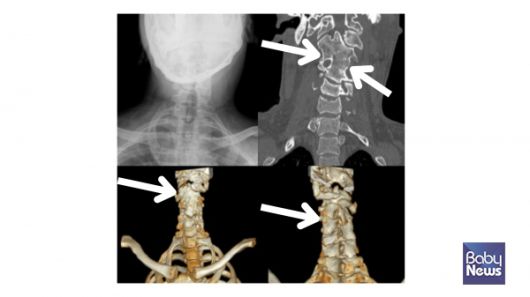

목뼈의 반쪽 척추. ⓒ임신영 |

목뼈의 분절 이상을 보이는 클리펠-파일 증후군. ⓒ임신영 |